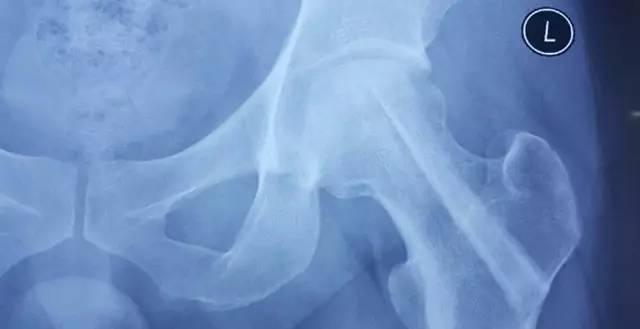

患者术前X光片,可以看到左侧的股骨头有一片区域已经出现了坏死

手术后,小张很快就可以下床走路,虽然在3-6个月之内还需要拄拐,但已经完全可以生活自理,疼痛的症状也已经完全消失。半年后复查,从小张的X光片上可以看到,股骨头内所植入的新骨已经完全愈合,股骨头也没有再出现塌陷。郭主任最后建议小张,可以完全扔掉双拐,开始正常的生活了!小张看到自己恢复的这么好,也特别高兴,自己对生活又重新充满了信心。

术后6个月复查,股骨头植骨的部分已经完全愈合,股骨头也未再继续塌陷